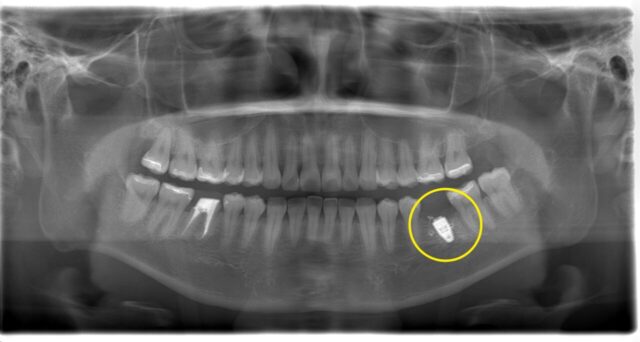

↓CT

根の先が黒くうつっており

かなり大きな「根尖病変」があります。膿が溜まって、歯を支えている骨が溶けている状態です💦

根管に神経の取り残しがあり感染根管治療をご提案しました。

抜歯と言われ大きな根尖病変がある右下の感染根管治療を行いました。

その歯は残念ながら保存はできず抜歯になってしまいましたが、インプラント治療を行いました。